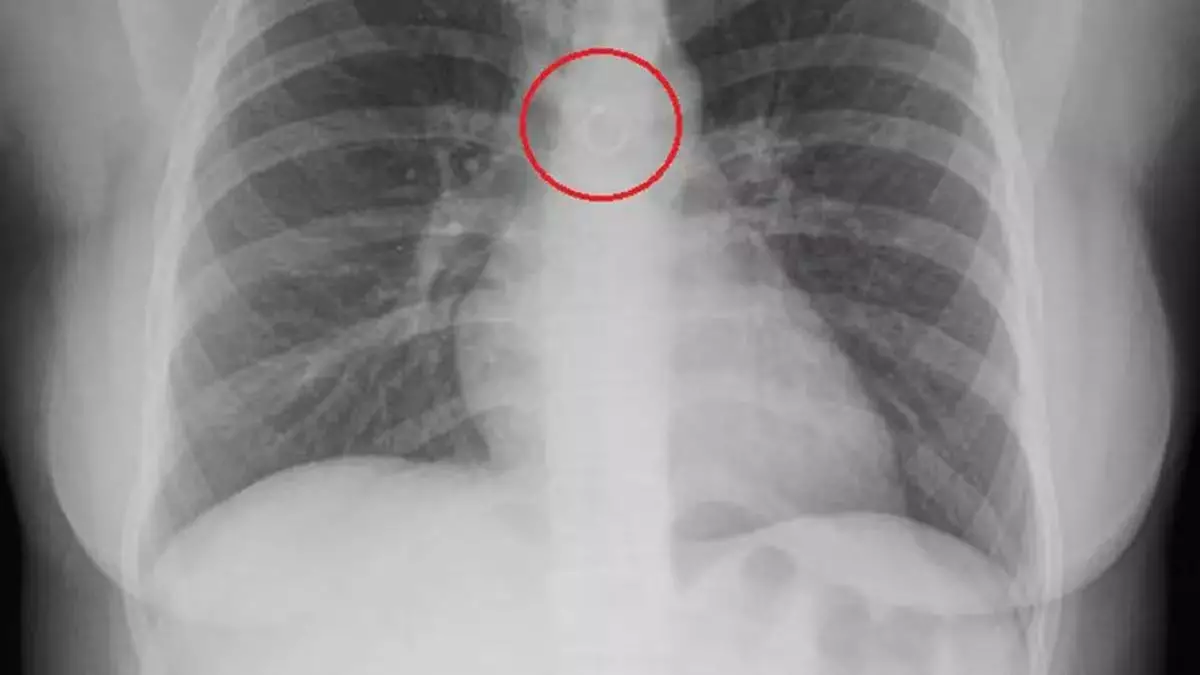

綜合外媒報導,墨西哥一名26歲女子巴拉哈斯(Monica Deyanira Cabrera Barajas)早前因持續咳嗽逾1個月未見好轉,遂前往醫院檢查。原以為只是普通小病,結果經X光檢查後發現,她的鼻環竟卡入肺部位置,甚至距離主動脈僅約0.5毫米,險些造成致命後果。

鼻環緊貼主動脈 誤吸入肺部恐致嚴重併發症

醫生透過影像檢查發現,巴拉哈斯的肺部內竟有一枚金屬鼻環,且緊貼主動脈,若位置稍有變動,隨時可能刺穿肺部或血管,引發氣胸或大量出血死亡。巴拉哈斯事後於TikTok分享自身經歷表示,起初並未察覺鼻環遺失,更未想到會被「吸入體內」,推測或因睡眠期間不慎令鼻環脫落並誤吸入呼吸道,最終進入肺部。